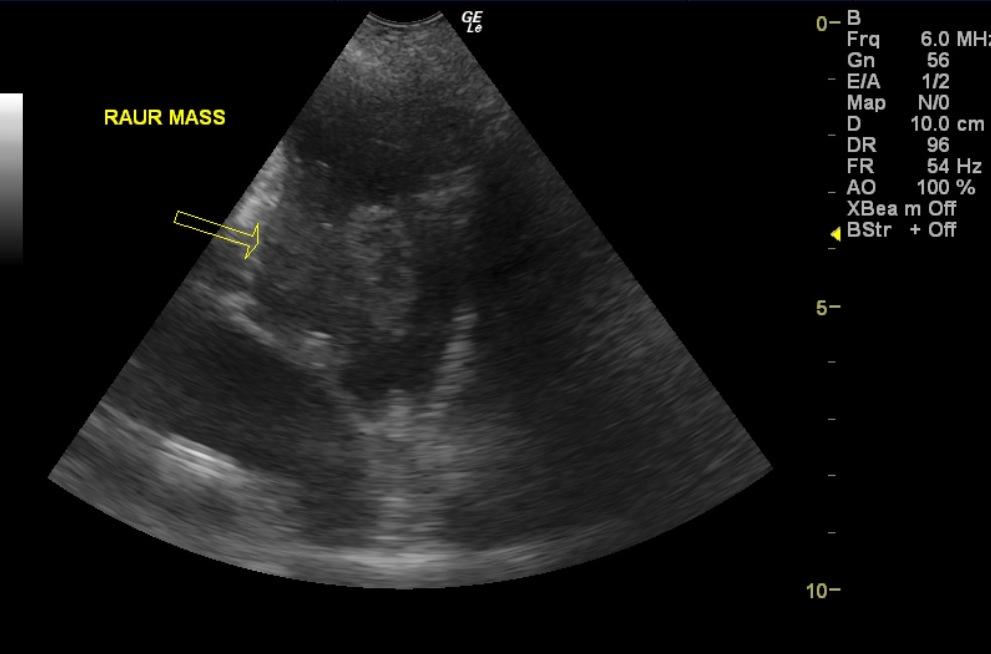

A 10-year-old SF Rottweiler cross was presented with a history of lethargy and not doing right. On physical examination depression and polypnea was evident. Abnormalities on serum biochemistry were elevated liver enzyme activity. Cardiomegaly was present on survey radiographs. Blood pressure was normal (140).